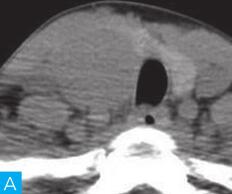

(1)滤泡性腺瘤:

滤泡性腺瘤是甲状腺最常见的原发性良性肿瘤,其与结节性甲状腺肿伴腺瘤样增生均可表现为高、等或低强化,在影像学上极难鉴别,但前者多为单发结节、平扫密度均匀(图2),而后者则多为多发结节、密度不均,一旦结节性甲状腺肿伴腺瘤样增生表现为单发结节,两者无法单纯通过影像学进行鉴别。

图2 滤泡性腺瘤:A.颈部CT横断面;B.颈部CT横断面增强